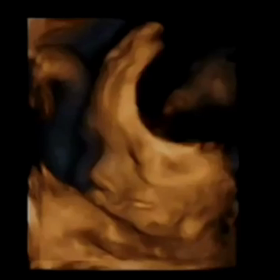

• 4D全編♡の画像

4D全編♡